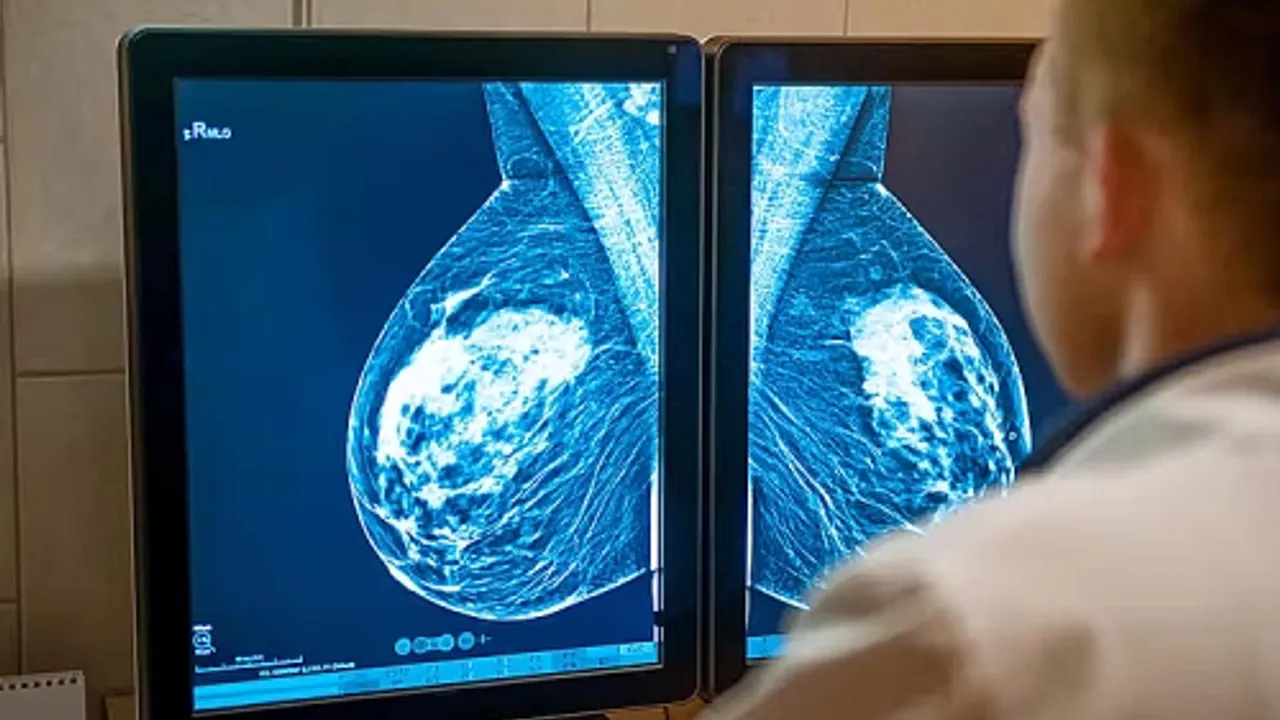

🔹 Düzenli taramayı ihmal etmeyin: Yaşa uygun meme muayenesi ve tarama programları, en etkili korunma yoludur.